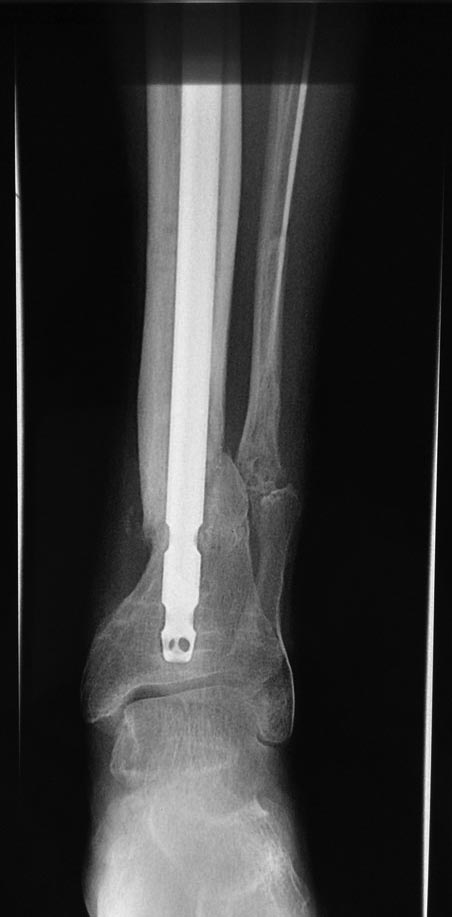

Уважаемые коллеги выразите Ваше мнение по следующему случаю. Молодой

человек, 27 лет, находится на лечении с диагнозом: Ложный сустав

большеберцовой кости в нижней трети, фиксированный интрамедуллярным

блокированным стержнем (12.02.2014 г), ложный сустав малоберцовой кости

в нижней трети левой голени, посттравматический артроз левого

голеностопного сустава 1 стадии. Укорочение левой нижней конечности на

В феврале 2014 г выполнил первым этапом: Фиксацию ложного

сустава в АНФ с восстановлением осей сегментов. Через семь дней БИОС с

рассверливанием.

После операции - вальгус голеностопного сустава. Гладкое течение

Через 6 мес. контроль - линия ложного сустава прослеживается, но имеется

периостальная костная мозоль.

Не хватает стабильности.